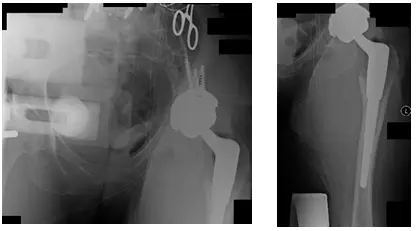

Removal of Left Hip and Placement of Spacer was performed in 2010. This procedure included resection of the femoral head of the lower left extremity, debridement of the acetabulum and femoral canal, along with the placement of an antibiotic spacer.

X-Rays taken the day of surgery. X-rays show a Left Antibiotic Spacer

Left Hip Spacer Removal and Left THA was performed early 2011.

X-Rays show revision left hip prosthesis post-operative